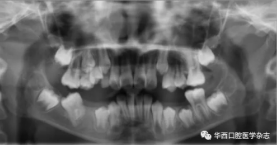

46牙開窗并將舌側扣粘接于近中面。用玻璃離子將鑄造板粘接在下頜,橡皮鏈通過83牙遠中的牽引鉤和46牙上的舌側扣相連,橡皮鏈牽引時對46牙產生一個順時針旋轉的作用力。術中牽引1個月時,見46牙產生順時針旋轉(圖5、6)。治療5個月時,46牙產生明顯的順時針旋轉,基本直立(圖7),由于此時下頜雙側乳尖牙脫落,下頜鑄造板無法固位,于是拆除矯治器,觀察隨診,待后期其余牙齒萌出后行全口固定正畸矯治。